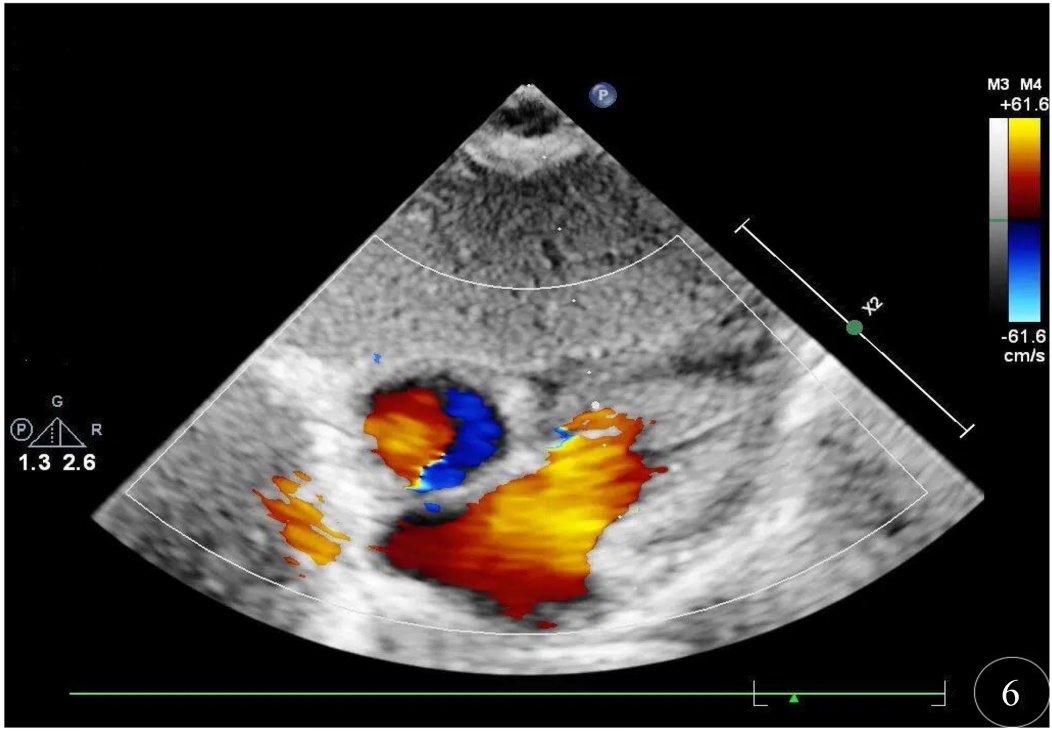

患儿,男,胎龄36周,出生体重3160 g,单胎,无窒息复苏史。系第2胎第2产,于暨南大学附属第一医院产科经阴道分娩娩出,出生时羊水清,自然啼哭,肤色稍青紫,反应、肌张力可、听诊心率 > 100次/分,Apgar评分:生后1 min为9分(肤色扣1分)、5 min、10 min均为10分。脐带水肿,绕颈一周,胎膜、胎盘无异常。血糖:3.0 mmol/L。血型:O型Rh阳性。其母血型为O型Rh阳性,妊娠期糖尿病,无感染史及用药史;其父血型为A型Rh不详;父母双方均否认地中海贫血及蚕豆病。生后予完善三大常规、生化肝功、感染二项、血气分析、DIC等多项检查。因患儿无相关临床表现,且母孕期无明确感染史,新生儿期未行TORCH血清学筛查(包括弓形虫、风疹病毒、巨细胞病毒、单纯疱疹病毒等)。其中,血常规 + 感染指标(出生第1天):超敏C反应蛋白0.33 mg/L,血小板计数204.00 × 109/L,白细胞计数20.23 × 109/L。血气分析(出生第1天):红细胞压积58%,氧饱和度90.2%。DIC检测:D-二聚体2130 ng/ml (FEU),纤维蛋白原2.98 g/l。降钙素原0.299 ng/mL。血常规、生化检查、肝功能、粪便常规 + OB、尿液分析均未见明显异常。血常规 + 感染指标(出生第3天):超敏C反应蛋白2.29 mg/L,血小板计数194.00 × 109/L,白细胞计数26.03 × 109/L。患儿生后查胆红素生理性升高,新生儿科予常规护理及蓝光照射退黄。生后查心脏彩超提示卵圆孔未闭(Patent Foramen Ovale, PFO) 1.9 mm,动脉导管未闭(Patent Ductus Arteriosus, PDA) 1.5 mm (见图1图2)。生后颅腔彩超检查提示颅脑回声及血流未见明显异常。听力筛查大致正常。结合患儿的症状、体征及辅助检查,临床诊断:早产儿、卵圆孔未闭、动脉导管未闭、胎儿和新生儿受母体情况的影响(妊娠期糖尿病)、胎儿和新生儿受脐带其他情况的影响(脐带水肿,绕颈一周)。该患儿出生后24小时内于暨南大学附属第一医院眼科行新生儿眼底筛查,眼底数码相机(RetCam III)检查可见:双眼视网膜平伏,视盘及黄斑发育可,双眼眼底颞上、颞下、鼻上、鼻下四个象限均可见大量类圆形或圆形出血灶散在分布,出血灶中心呈白色点状,约20~25处,最大出血灶直径可达1.5 PD,主要分布在视网膜后极部;视网膜血管鼻侧已达睫状体周边部,颞侧未达睫状体周边部。(见图3图4)。患儿双眼眼底检查未见早产儿视网膜病变(Retinopathy of Prematurity, ROP)体征(按2014年版指南判定标准),但双眼可见大量Roth斑,予常规表面护理及随访观察。计划随访时间为第1周,实际完成于第2周。生后第2周我科随访,该患儿眼部检查:双眼角膜透明,瞳孔等大等圆,双眼眼底视网膜平伏,视盘边界清晰,血管走行正常,双眼周边视网膜已基本血管化,黄斑发育良好,后极部及周边部均未见明显渗出及出血灶(见图5)。生后2月余于我院门诊复查心脏彩超提示卵圆孔及动脉导管均闭合,心内结构及血流未见异常(见图6图7)。

Figure 6. The infant’s cardiac ultrasound examination: no structural abnormalities of the heart. Color Doppler Flow Imaging (CDFI) reveals no shunting at the atrial or ventricular levels

6. 示患儿心脏彩超检查:心内结构未见异常。彩色多普勒血流成像(CDFI)房室水平未见分流

Figure 7. The infant’s cardiac ultrasound examination: no abnormalities of the aorta or pulmonary artery. Color Doppler Flow Imaging (CDFI) reveals no evidence of regurgitant flow

7. 示患儿心脏彩超检查:主动脉、肺动脉未见异常。彩色多普勒血流成像(CDFI)未见血液返流